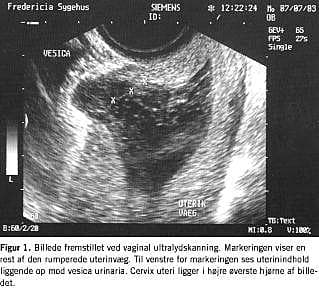

På grund af vedvarende blæretømningsbesvær blev patienten vaginalskannet efter tre uger. Man fandt da en 2 cm defekt i forreste del af isthmus med udbugning af uterinindhold ind mod blæren (Figur 1 ).

Der var således tale om ruptur af uteruscikatricen efter tidligere sectio.